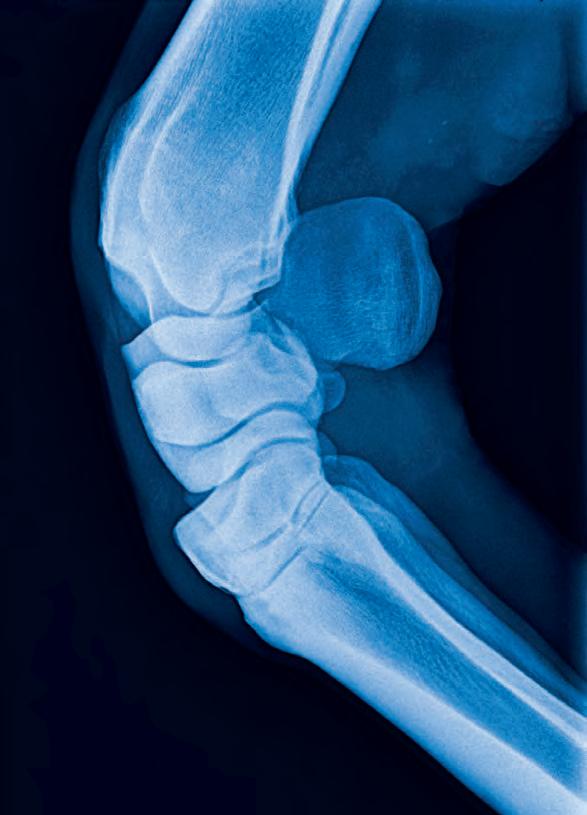

Bilateral hind cannon radiographs of X XXXX XXXXXX were taken on 14th April 21 and again 17th May 21 and 14th June 21. Initial radiographs showed a 32mm longitudinal non displaced left mid cannon saucer fracture extending 6mm into the dorsal cortex and a 44mm longitudinal displaced fracture right mid cannon 5.5mm in depth mid dorsal cortex associated proximally with a 27mm x 6.5mm secondary fracture (see right). Initially, surgical removal was recommended of the R H fracture fragment. A second series was taken on 17th May and third series on 14th June see right. Both fractures have attached and integrated with the parent bone with minor surface enthesophyte formation and periosteal activity evident.